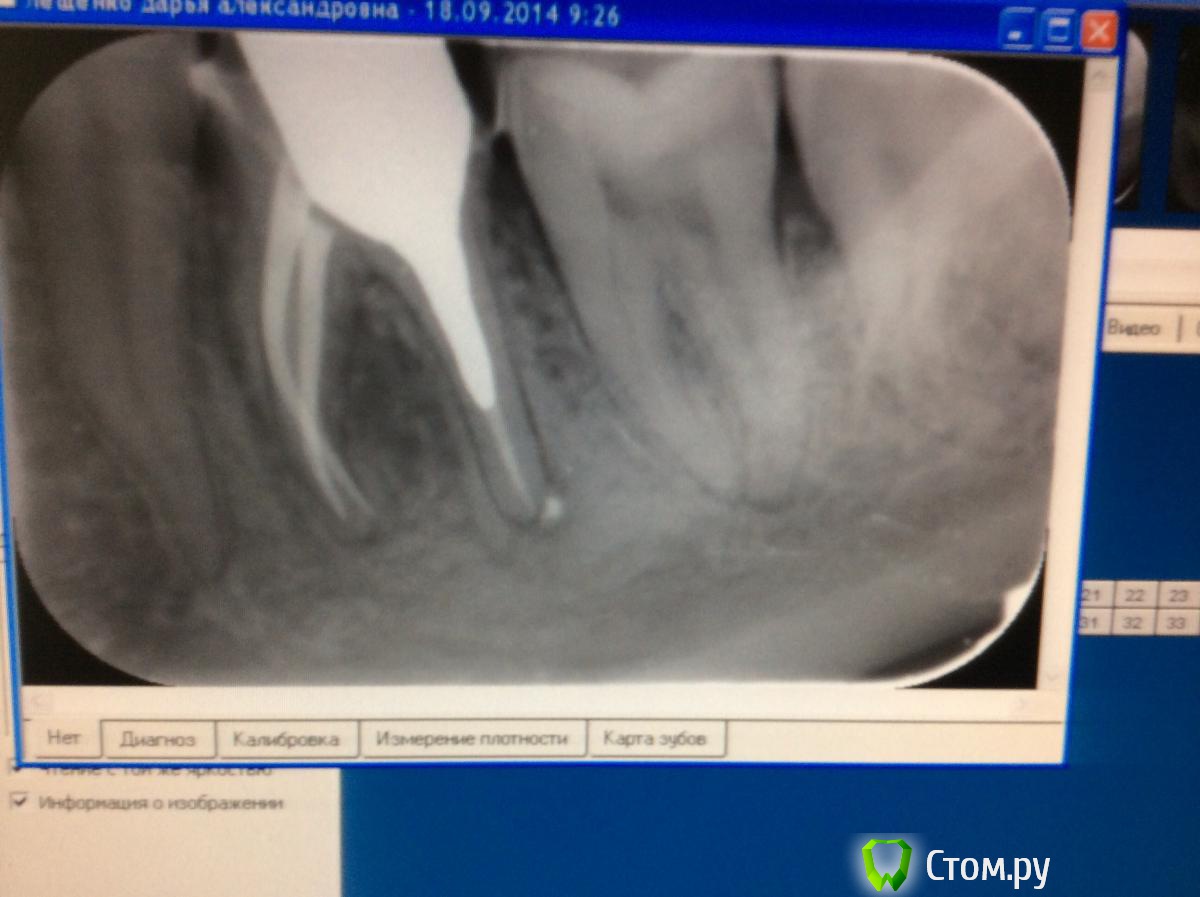

Bratok Опубликовано 18 сентября, 2014 Автор Поделиться Опубликовано 18 сентября, 2014 (изменено) Коллеги, подскажите, пожалуйста, причины возникновения болей после фиксации временной коронки. Аллергия на пластмассу? Остатки цемента могли остаться между зубами и вызвать локальный пародонтит? Зуб мог сломаться? При жевании пациент на боль не жалуется. Началось перед сном спустя несколько дней после фиксации времянки. Как будто что то давит, со слов пациента, боль постоянная. При пальпации переходной безболезненно. При перкуссии пациент отмечает дискомфорт со стороны язычных бугров. Могла быть перегрузка после фиксации? Зуб долгое время "не жевал". Снимки процесса. (Первый снимок - ситуация до лечения)Фото фиксации времянки примерно 5 дней назад.P.S. Извиняюсь за качество снимков..Размер ножки вкладки был продиктован уже имеющейся ситуацией до лечения. Изменено 18 сентября, 2014 пользователем Bratok Ссылка на комментарий